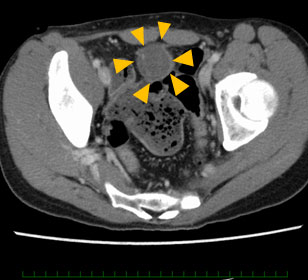

図 矢頭:CT画像上の尿膜管がんの腫瘤(骨盤内)

症状などから尿膜管がんが疑われる場合には、腫瘍の性状や発生した場所を確認するため膀胱鏡検査や、CTやMRIなどの画像診断を行います。尿膜管がんの確定診断のためには、膀胱鏡を用いて腫瘍の一部を採取(生検)して、病理診断を行うことが必要です。